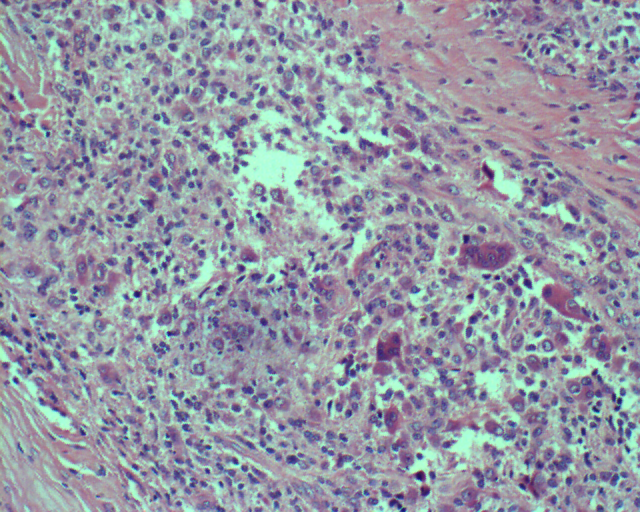

2.镜下

白色区由成熟的梭形或卵圆形细胞产生的纤维基质呈旋转形状组成。黄色区则由大的充满空泡的大吞噬细胞或组织细胞组成。红棕色区成熟的基质细胞呈旋涡状排列,分散存在着多核巨细胞。其胞浆中含有含铁血黄素。组织学中以组织细胞占主要成分时有人称其为腱鞘黄色瘤。当漩涡状基质细胞结缔组织为主时有人称其为良性纤维组织细胞瘤。

组织学特点:见组织细胞样细胞、泡沫细胞及多核巨细胞。